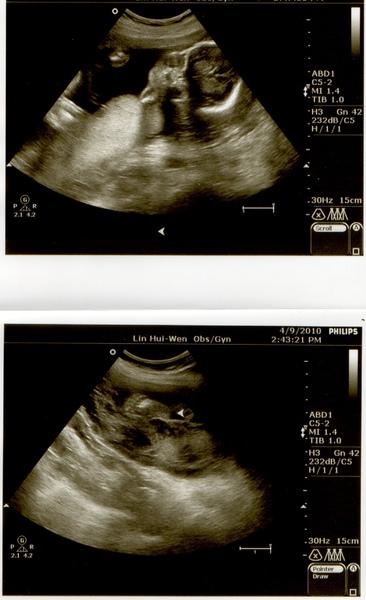

【第四次產檢】21W寶貝波咕波咕愛游泳

書上說寶寶約4-5個月時,媽媽可以感受到胎動。我們家寶寶還滿準時的,4個半月的時候開始會波波的動來動去,有時候游左邊有時候游右邊,有一下沒一下的一踢一踢,還挺可愛的(心)。

【第三次產檢】16W虎虎還是虎妞?

本次檢查之前,我跟J老大一直在猜小寶貝現在身高多了呢?J老大猜20cm,我猜16cm,結果答案揭曉~17cm,寶寶看起來頭好圓,腿也很長,應該有遺傳到他兩個高人一等(我174,J老大180)的爸媽吧XD。